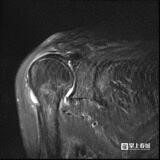

术中

该本领通过将患者自己的肱二头肌长头腱转位固定,替代受损的上要津囊进行重建,告捷惩办了弘远肩袖挫伤无法径直缝合的逆境,ag真人多台百家乐的平台官网具有操作方便、成果更佳、用度低等优点。